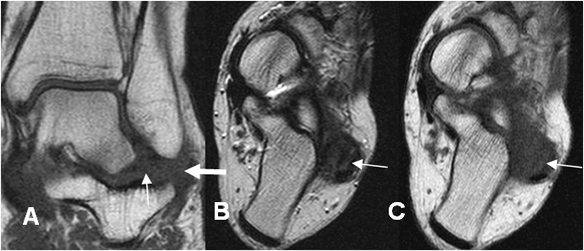

Fig 64 B. Esguince grado III.

RM axial en T2. Ruptura completa del LPAA, con líquido fuera de la articulación.

Fig 64 C. Esguince G III.

RM coronal en STIR. No visualización de los ligamentos peroneoastragalino, ni peroneocalcaneo, por ruptura completa.